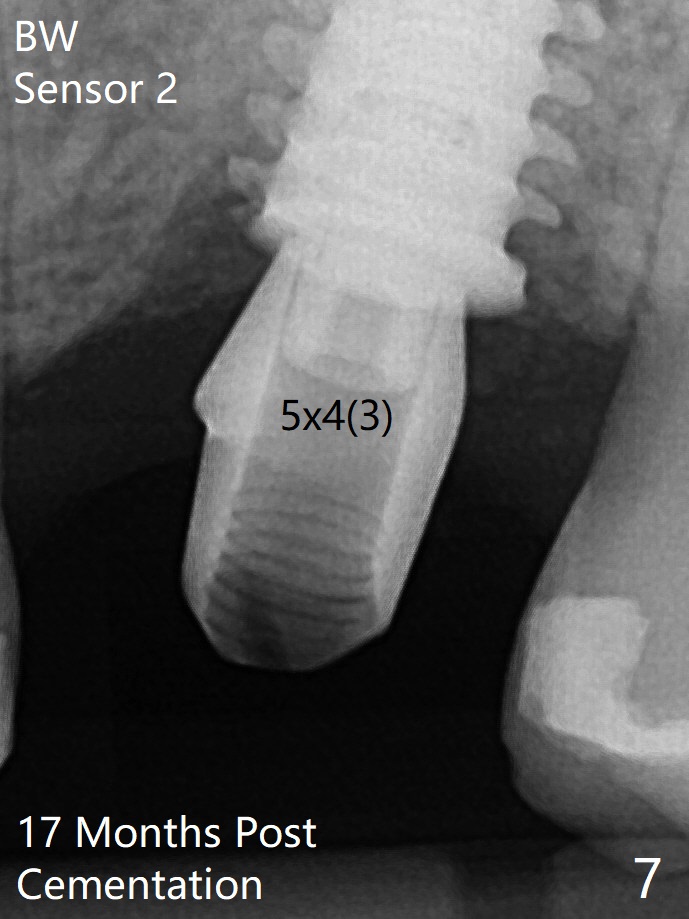

After extraction of the tooth #14 with palatal swelling (Fig.1 *), the septum (S in Fig.2) is found to be thin. Sequential osteotomy quickly deviates to the palatal socket. In spite of using Lindamann bur to remove the bone from the buccal portion of the osteotomy, the apical end of a 5x9 mm dummy implant slides into the palatal socket with the coronal end placed as buccal as possible for restoration (Fig.2 (poor trajectory)). Further use of Lindamann bur for buccal bone removal is not feasible, since the buccoapical portion of the osteotomy starts to be perforated with apparently intact sinus membrane. With insertion of Vanilla graft for sinus lift through the buccoapical portion of the osteotomy mentioned above, a 6x11 mm implant is placed with the same trajectory (Fig.2, <40 Ncm). With placement of a 6.5x4(3) mm abutment (off angle) and of Vanilla graft in the remaining sockets (Fig.2 *), periodontal dressing is applied. When the dressing is dislodged for the 2nd time (12 days postop with healing socket), an angled abutment 5x15 degree, 3 mm cuff, is placed and a provisional is fabricated. There is no sign of sinus infection. The provisional and angled abutment become loose without sinus infection 2 months postop. A 5.5x3 mm healing abutment is placed with light tenderness. If this case turns to be failure, do not stick an immediate implant from potentially infected socket into the sinus in the future. The socket appears to heal 11 months postop (Fig.4). Later a 5x4(3) mm abutment is placed for final restoration. The palatal margin is low. The abutment screw is loose <2 months post cementation, probably due to deep placement and poor trajectory (buccal). It becomes loose again 4 months later. Prior to retightening, a 6 mm profile drill is used. BW shows no bony interference (Fig.5 (opposing tooth occlusal wear; bruxism)), while PA shows the buccal bone, suggesting poor trajectory. The abutment is loose for the 3rd time 17 months post cementation. When the crown/abutment is removed, the hex is worn. After proximal reduction, the crown/abutment feels to be unable to be re-seated. When the crown is sectioned, the abutment itself is incompletely seated (Fig.7,8). The mesial crest appears to interfere with seating (Fig.8). When the 5.2x3 mm dummy abutment is seated, the buccal margin is subgingival, while the palatal one supragingival, suggesting the buccally tilted implant (guided surgery essential). A 4.5x4(4) mm pair abutment seems to be seated completely (Fig.9). The hex of the 5x4(3) mm abutment is worn, but the abutment seems to be able to be seated completely (Fig.11), although not so crisply (easily) as the unworn one clinically. Return to Upper Molar Immediate Implant, Prevent Molar Periimplantitis (Protocols, Table), Armaments Screw Xin Wei, DDS, PhD, MS 1st edition 06/26/2018, last revision 12/20/2020